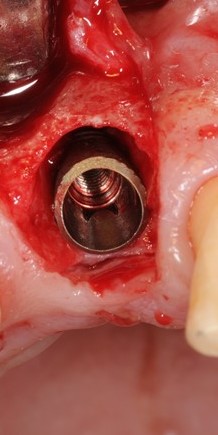

Так вот, чрезмерная атрофия альвеолярного гребня может лишить нас возможности имплантации — нам просто не хватит объемов костной ткани для нормальной установки имплантов. Однако, эта проблема решаема — существует целый ряд методик остеопластики (включая синуслифтинг), позволяющих восстановить любой объем костной ткани в в любом участке зубного ряда с высокой степенью эффективности. И, как правило, хорошие врачи в хороших клиниках так и поступают:

Увы, но подобные методики подходят не всем. Скажем так, я бы десять раз подумал прежде, чем проводить остеопластику пациенту, которому больше 80 лет, у которого есть серьезные проблемы со здоровьем. Также было бы сложно восстановить до необходимого полностью беззубый альвеолярный гребень со значительной атрофией по высоте:

Их можно установить в минимально возможный объем костной ткани, где установка обычных взрослых имплантов невозможна без предварительной остеопластики. В некоторых случаях они даже позволяют избежать синуслифтинга, что, согласитесь, звучит очень заманчиво.